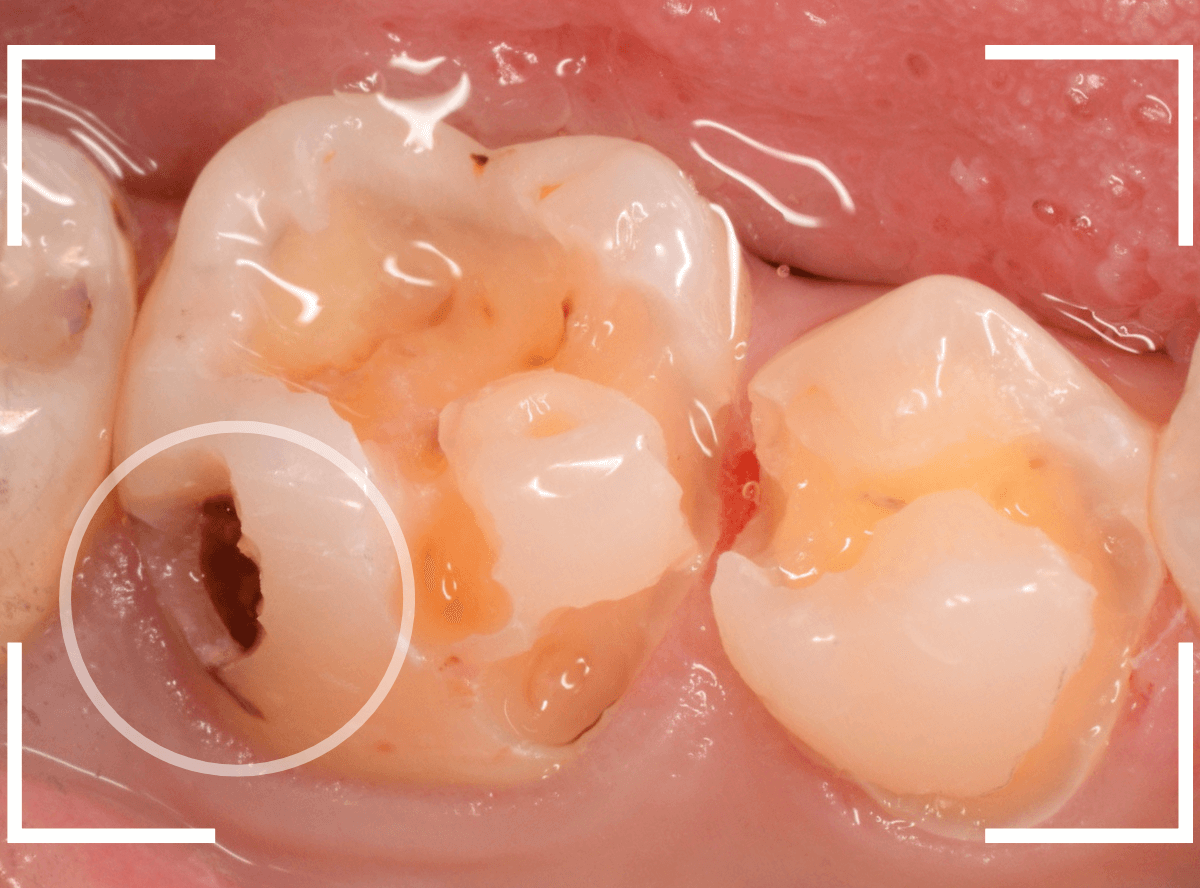

Case.10 レントゲンに写らない側面の虫歯を、少しずつ削って調べる

こちらも、虫歯が歯のあちこちで進行してしまっている患者さんのケースです。

特に側面の虫歯が深そうです。

側面にできた虫歯はレントゲン写真では診断しづらくやっかいです。

今回は「見るからに深そう」ですが。

さすがにレントゲン写真でも虫歯がありそうな事は確認できますが、実際にどうなってるのかはあまりはっきりわかりません。